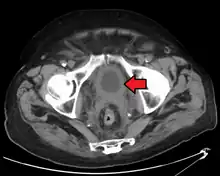

CT Urography shows multiple tumors -